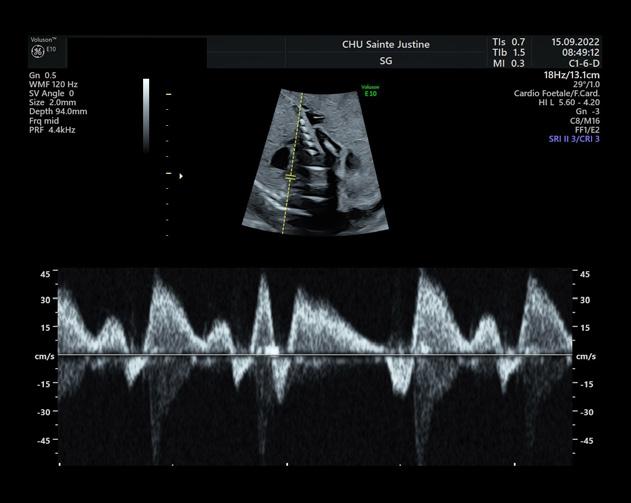

Électrophysiologie médicale

Tétralogie de Fallot : combinaison de quatre anomalies cardiaques congénitales

Assistante-chef technologue en électrophysiologie médicale spécialisée en échographie cardiaque

Hôpital Jean-Talon, CIUSSS du Nord-del’île-de-Montréal

La tétralogie de Fallot est la plus fréquente des cardiopathies congénitales cyanogènes, représentant près de 8 % d’entre elles. Cette malformation tire son nom d’Étienne-Louis Arthur Fallot, qui l’a décrite en 1888.

La tétralogie de Fallot se caractérise par quatre anomalies distinctes, comme ÉtienneLouis Fallot, anatomopathologiste, les avait observées lors d’autopsies. En réalité, deux de ces anomalies suffisent à expliquer la physiopathologie de cette malformation, les deux autres n’étant que des conséquences. Cette introduction vise à offrir un aperçu des caractéristiques cliniques, des défis diagnostiques et des approches thérapeutiques actuelles de cette pathologie (figure 1 ).

Anomalies anatomiques de la tétralogie de Fallot :

■ Rétrécissement de l’artère pulmonaire.

■ Hypertrophie du ventricule droit, qui compense la pression exercée par le rétrécissement de l’artère pulmonaire.

■ Communication interventriculaire entre les ventricules droit et gauche.

■ Malposition de l’aorte à droite, chevauchant le septum interventriculaire. Ce déplacement partiel au-dessus du ventricule droit résulte du défaut d’alignement à l’origine de la communication interventriculaire.

Cœur normal Tétralogie de Fallot

Dextroposition de l’aorte Sténose pulmonaire

Communication inter-ventriculaire

Hypertrophie ventriculaire droite

Figure 1 : Différence entre un cœur normal et un cœur ayant une malformation appelé la tétralogie de Fallot.

Anomalies principales :

■ Sténose (rétrécissement) de la voie d’éjection du ventricule droit : Cette sténose peut se situer au niveau de l’infundibulum pulmonaire, de l’anneau pulmonaire ou du tronc de l’artère pulmonaire (avant la bifurcation en deux artères pulmonaires). Le rétrécissement peut être localisé ou prédominer sur une de ces trois parties dans les formes mineures. En revanche, dans les formes sévères, il peut s’étendre à l’artère pulmonaire, y compris aux branches droite ou gauche.

Claudia Hernandez t.e.p.m.

■ Communication interventriculaire (CIV) : Cette communication se situe près de l’origine des gros vaisseaux, notamment de l’aorte. Elle résulte d’un mauvais alignement entre l’aorte et la portion musculaire du septum interventriculaire.

Ces caractéristiques anatomiques et physiopathologiques permettent de comprendre la complexité et la gravité de la tétralogie de Fallot, nécessitant une prise en charge médicale spécialisée.

Signes et symptômes

Nouveau-né et nourrisson

À la naissance, le nouveau-né est souvent bien coloré, rose, et ne présente pas de gêne particulière. Cependant, la présence d’un souffle cardiaque systolique, perçu dès l’auscultation en salle d’accouchement, attire l’attention. Un souffle d’apparition précoce nécessite une échocardiographie d’urgence.